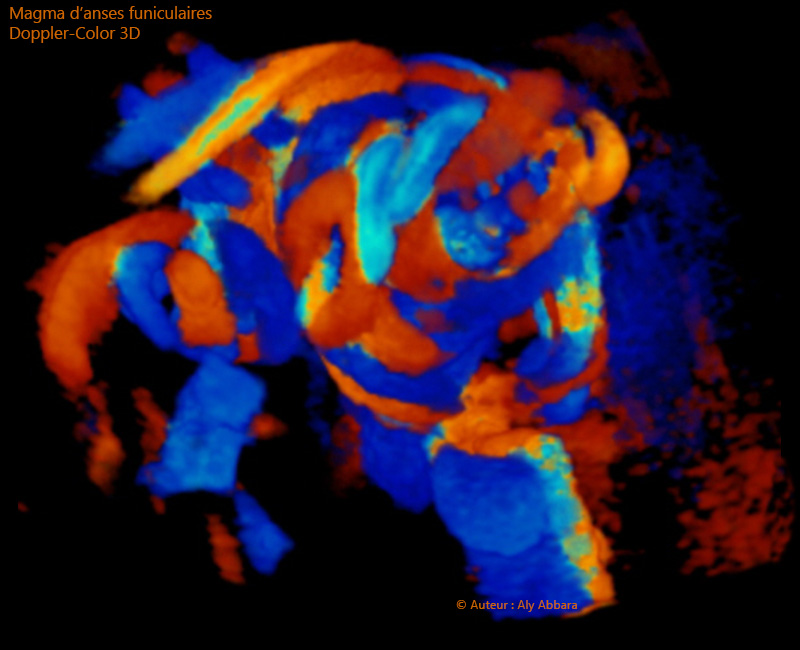

Doppler-Couleur 3D : magma d'anses funiculaires

Image échographique en 3D d'un amas d'anses du cordon ombilical mises en évidence en utilisant le Doppler-couleur.

La couleur rouge permet d'identifier les flux sanguins se dirigeant vers la sonde émetteur des ultrasons ; la couleur bleu met en évidence les flux sanguins s'éloignant de la sonde et enfin, les couleurs intermédiaires sont des aliasings (résultantes de la distorsion des flux sanguins).

Aliasing : en acoustique, effet indésirable de distorsion du son lors de l'échantillonnage.

Ce code couleur échographique du phénomène Doppler-Couleur est à l'inverse du code couleur des phénomènes astronomiques : les étoiles s'éloignant de nous prennent la couleur rouge, par contre, les étoiles s'approchant de nous prennent la couleur bleu.